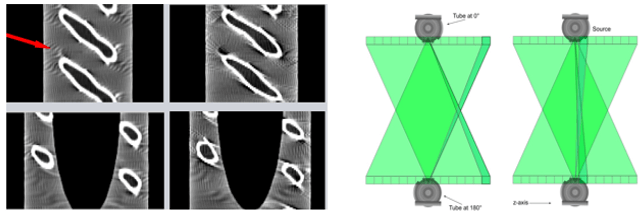

Helical Artifact

Helical artifacts can sometimes be seen with faster scanning techniques. In general, the same artifacts are seen in helical scanning as in sequential scanning. However, there are additional artifacts that can occur in helical scanning due to the helical interpolation and reconstruction process. The artifacts occur when anatomic structures change rapidly in the z-direction (ie, at the top of the skull) and are worse for higher pitches. Helical and multisection technique artifacts are produced by the image reconstruction process.

This set of artifacts shows a fast anatomical variation in the Z direction.

Cone-Beam Artifact

When the collimation is greater than the Z-axis, the detectors will receive less information. This distorts the image during the tube rotation. When mathematical algorithms are used the artifact can be corrected. High collimation highlights the cone-beam artifacts.